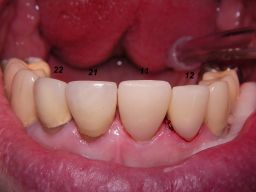

Der Abschluß der Sitzung am 17.2.06 waren 2 provisorische Kronen auf Zahn 11, 12. Das provisorische Material war hier wegen der besseren Farbanpassung Herculite XRV. Rechts sieht man auch die alten Kronen 21 und 22 und die von mir früher reparierten Randdefekte. |

Links das Kontrollfoto nach der Sitzung am 17.2.06. Damit war die Vorbehandlung in diesem Fall abgeschlossen. | |